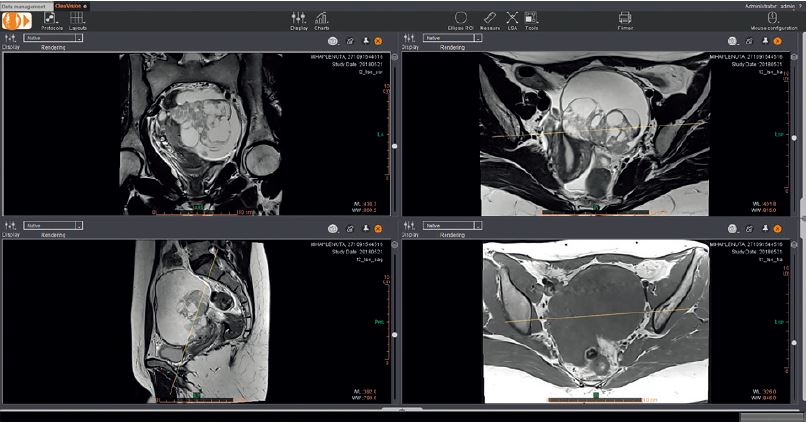

Переглядач на платформі Еnterprise завдяки комбінованій візуалізації трьох площин Т2, Т1 із насиченням жиру та без нього, дозволяє підтвердити, що ураження пов’язано з яєчником та що не знайдено наявності жиру (тип ураження дермоїд) або крові (рис. 2). Опція Olea IVIM дає змогу обчислювати дифузійно-зважені синтетичні зображення (в т.ч. з високими значеннями b), щоб полегшити діагностику більшої частини уражених тканин (рис. 3).

Рисунок 2